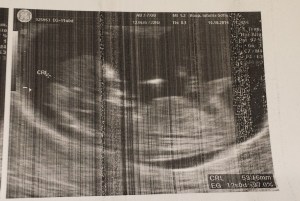

Hoy no tengo muchas cosas para decir, pero todas importantes. Sigo sintiéndome muy cansada pero muy contenta. Ya se me nota la barriga y he aumentado dos kilos. Me han hecho la primera ecografía de la seguridad social y ha salido todo muy bien, he visto a mi peque estirándose, moviéndose, me han mostrado sus manos y pies, han realizado el tiple screening, (en donde además de ver el latido del corazón y hacer las medidas regladas; cabeza, abdomen y fémur para establecer la edad gestacional, está ecografía permite diagnosticar grandes malformaciones y determinar el grosor del pliegue nucal).  Ha salido riesgo bajo, así que todo fenomenal.

El bebé ya mide 6 cm y todo va acorde con la edad gestacional.

La medida del pliegue nucal, (técnicamente llamado traslucencia nucal) se considera un marcador de alteraciones genéticas como el síndrome de Down o el Turner, y es la zona que queda por detrás del cuello del feto. Cuando el grosor es mayor de la media normal (generalmente en torno a los 3 milímetros en la semana 12) puede existir mayor riesgo de que se asocie a un feto con síndrome de Down y por tanto, recomendarse la realización de una amniocentesis. Esta medida se combina con  la edad de la madre y el resultado de una analítica, creando así el llamado «triple screening» tan importante en la semana 12.